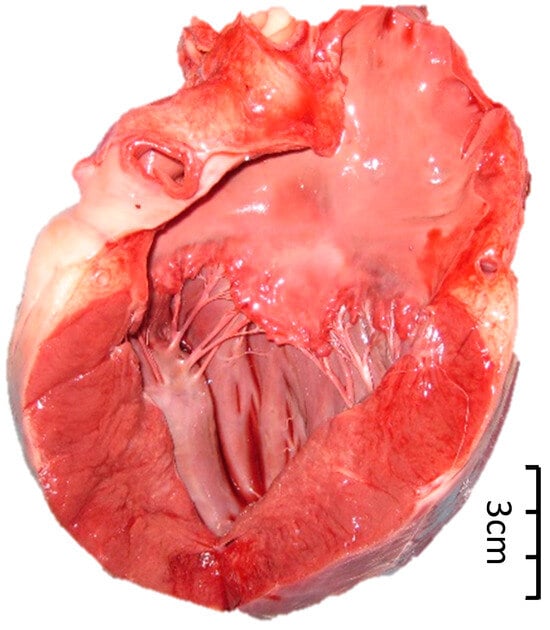

- Bando, M.K.H.; Nelson, O.L.; Webster, N.; Ramsay, J.D.; Bacon, H.J.; Sellon, R. Aortic aneurysm, dissection, and rupture in six bile-farmed bears. J. Zoo Wildl. Med. 2018, 49, 738–747. [Google Scholar] [CrossRef]